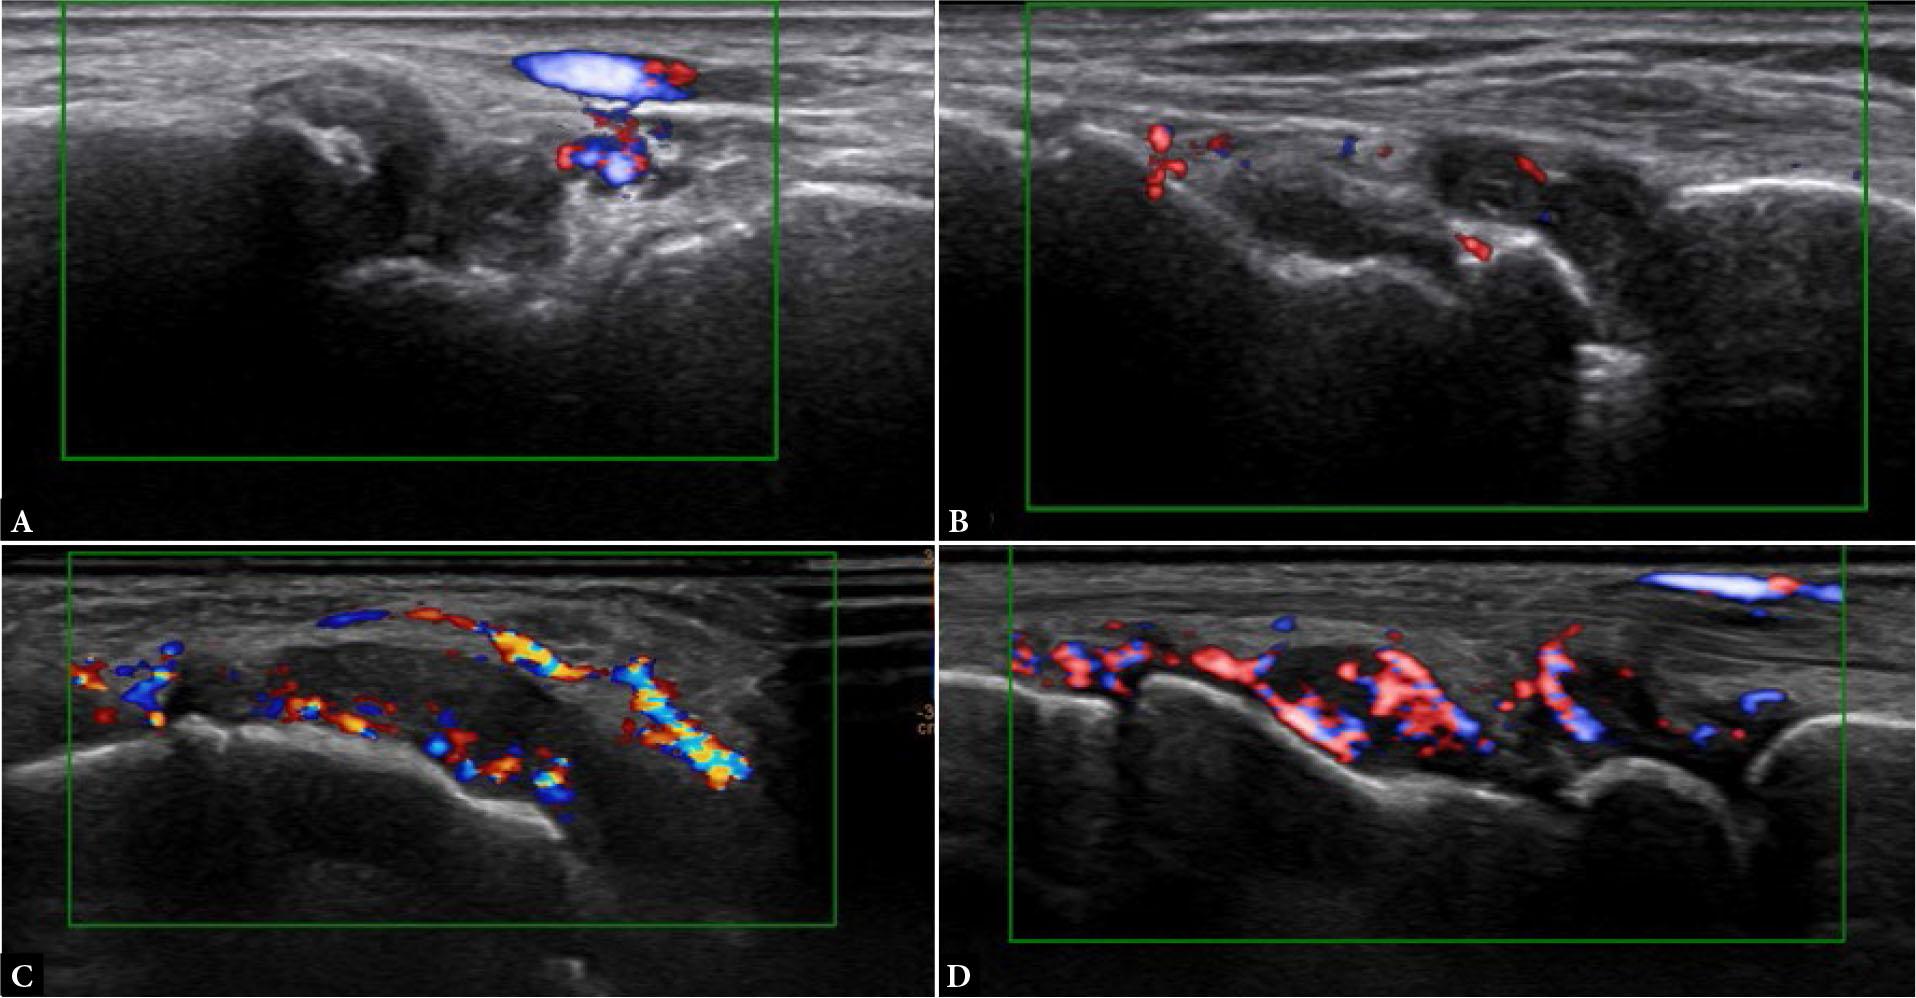

Fig. 5.

Power Doppler synovitis grading. Long-axis PDUS of the wrist joint shows grade 0 –no flow (A); grade 1 – single-vessel signal (B); grade 2 – less than half of the area of the synovium-filled with vessels (C); grade 3 – more than half of the area of the synovium filled with vessels (D). Note: the Doppler signal in (A) is from the periarticular vessels and not the synovium